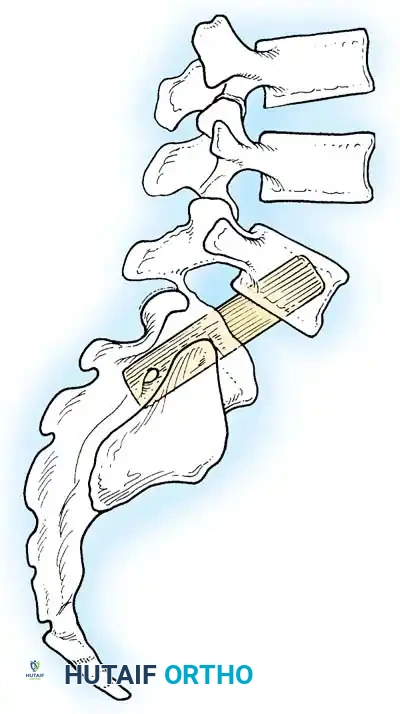

5. Management of High-Grade Slips: In Situ Fusion

In the rare adult presenting with a high-grade slip (Grade III or IV), aggressive reduction maneuvers carry an unacceptably high risk of L5 nerve root stretch injury (neurapraxia). In these scenarios, an in situ fusion is preferred.

- Bohlman Technique: This technique involves a posterior decompression combined with a transsacral transvertebral fibular dowel graft.

- A trajectory is drilled from the posterior aspect of the S1 vertebral body, traversing the S1 endplate, across the disc space, and into the anteriorly translated L5 vertebral body.

- A structural fibular allograft or titanium dowel is impacted across this trajectory, effectively locking the L5 vertebra to the sacrum in its current position, preventing further shear while avoiding the neurological risks of reduction.